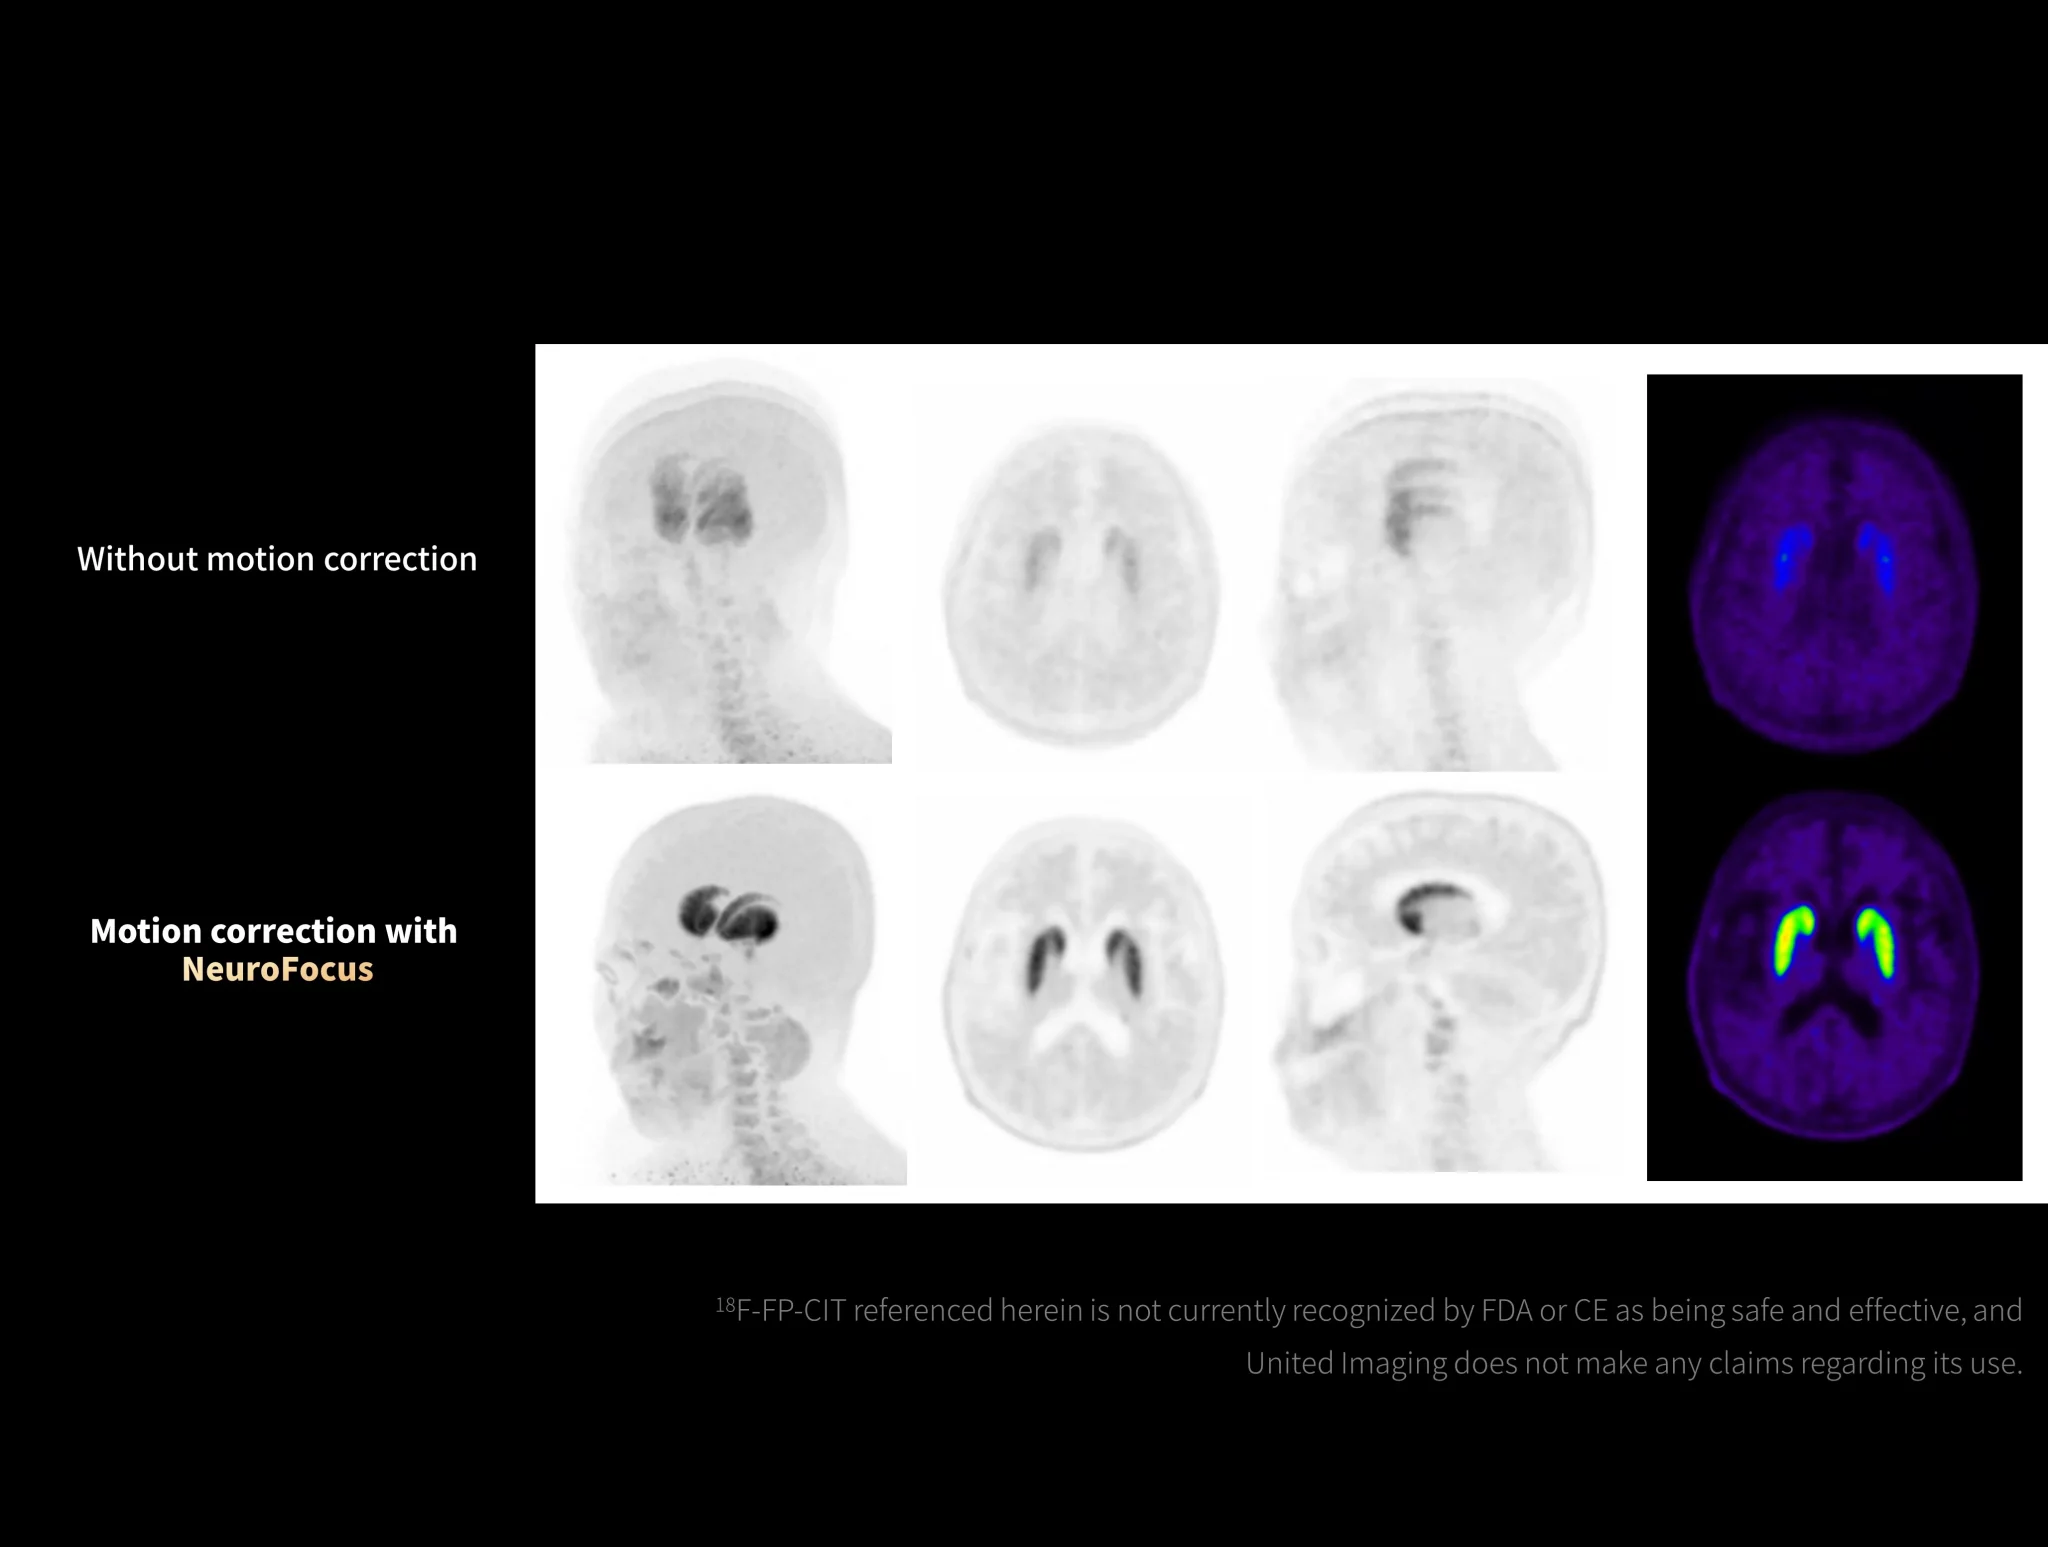

uMI Panorama is greatly empowered by innovative technologies integrated into the uExcel SCAN and uExcel CARE workflows. With uExcel SCAN, you can rely on intelligent positioning, scanning, and motion correction to streamline your routine tasks and maximinze your work efficiency. And uExcel CARE features uExcel DPR and uExcel AIIR reconstruction algorithms to ensure clear images even at low doses.